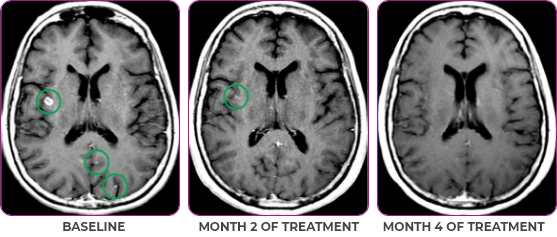

Response in primary and metastatic lesions1

MRIa imagery of the lungs. Arrow indicates large target lesion in left lung.1

SCAN 1: LUNG

MRIa imagery of the brain. Arrow indicates large target lesion in left lung.1

aMRI, magnetic resonance imaging.

Images courtesy of Dr Fabian Pitoia.

Response to VITRAKVI1

- After 8 weeks on VITRAKVI, all target lesions had disappeared, demonstrating a complete response

- The complete response was sustained over 11 months of treatment with VITRAKVI

- Patient experienced Grade 1 fatigue and mild hepatic enzyme elevation